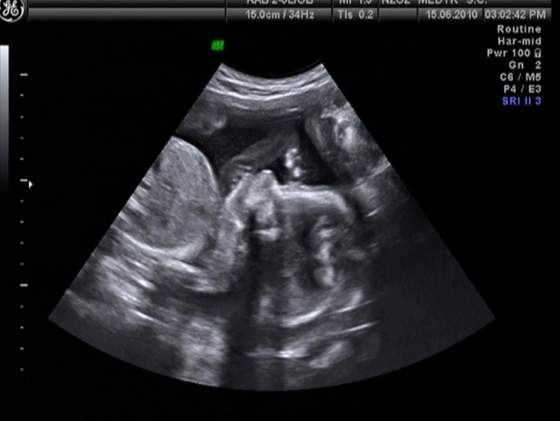

Dziewczynki a to moje małe szczęście. Troszke niewyraźne są ,ale profil widać :) i mamusi się on bardzo podoba :)

Po ostatniej wizycie mam taką fotkę:

No to ja wrzucę najnowsze fotki z wczoraj :-)